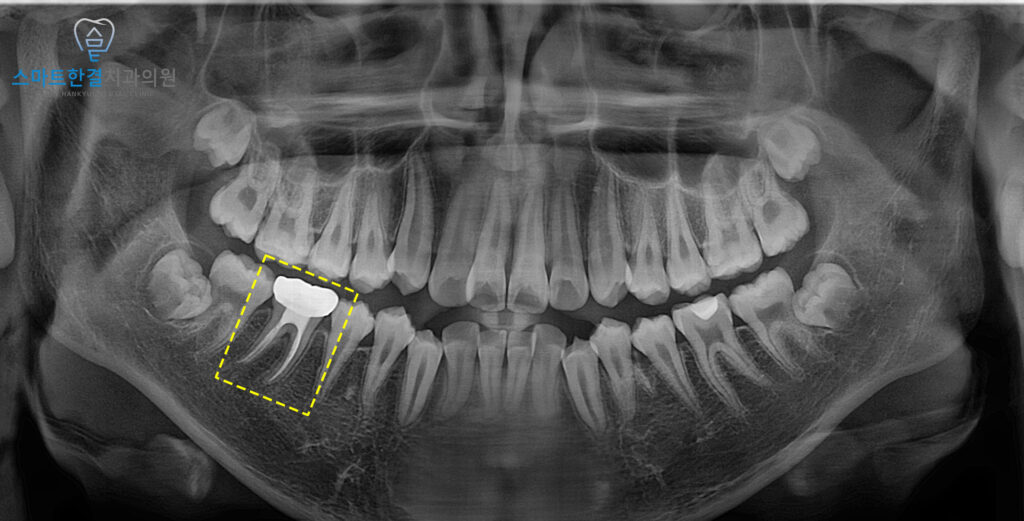

위 환자분께서는 14세 남아로,

오른쪽 아래 안쪽 잇몸에 부기가 발생하여

본원에 내원해 주셨는데요.

이를 확인하기 위해

정밀 검사를 진행한 결과,

치근분지부 쪽으로 방사선 투과상이

더 진행된 것을 확인할 수 있었는데요.

즉, 염증이 여전히 치아와

주변 조직으로 확산되어 있었고,

추가적인 치료가 필요한 상태였어요.

정밀한 엑스레이 사진을 촬영해본 결과,

염증이 뚜렷하게 나타났으며

치아 뿌리 주변으로 염증이 확산된 상태임을

확인할 수 있었어요.

치수생활력이 상실되어 있어,

치아의 뿌리가 제대로 성장하지

못했을 가능성이 있었는데요.

25.02 / 26.02

화서동치과 스마트한결치과의

신경치료 전후 사진이에요.